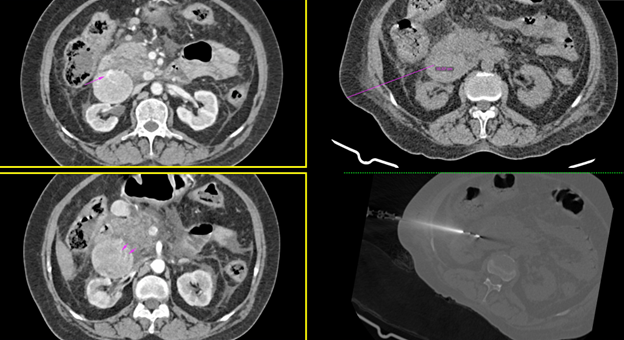

55 Y/ Female patient with abdominal pain with two avidly enhancing lesions with increased vascularity were noted just posterior to the duodenum.

Procedure details:

CT-guided biopsy of the soft tissue lesion was done from the right side in a semi left lateral decubitus position under local anesthesia. Challenge faced in supine position was the biopsy needle touching the CT table.

Needle used: 17G introducer needle. 18 G biopsy gun.

No complications post procedure. No bleeding at the site.

The patient tolerated the procedure well. Inj Pause given to the patient post biopsy.